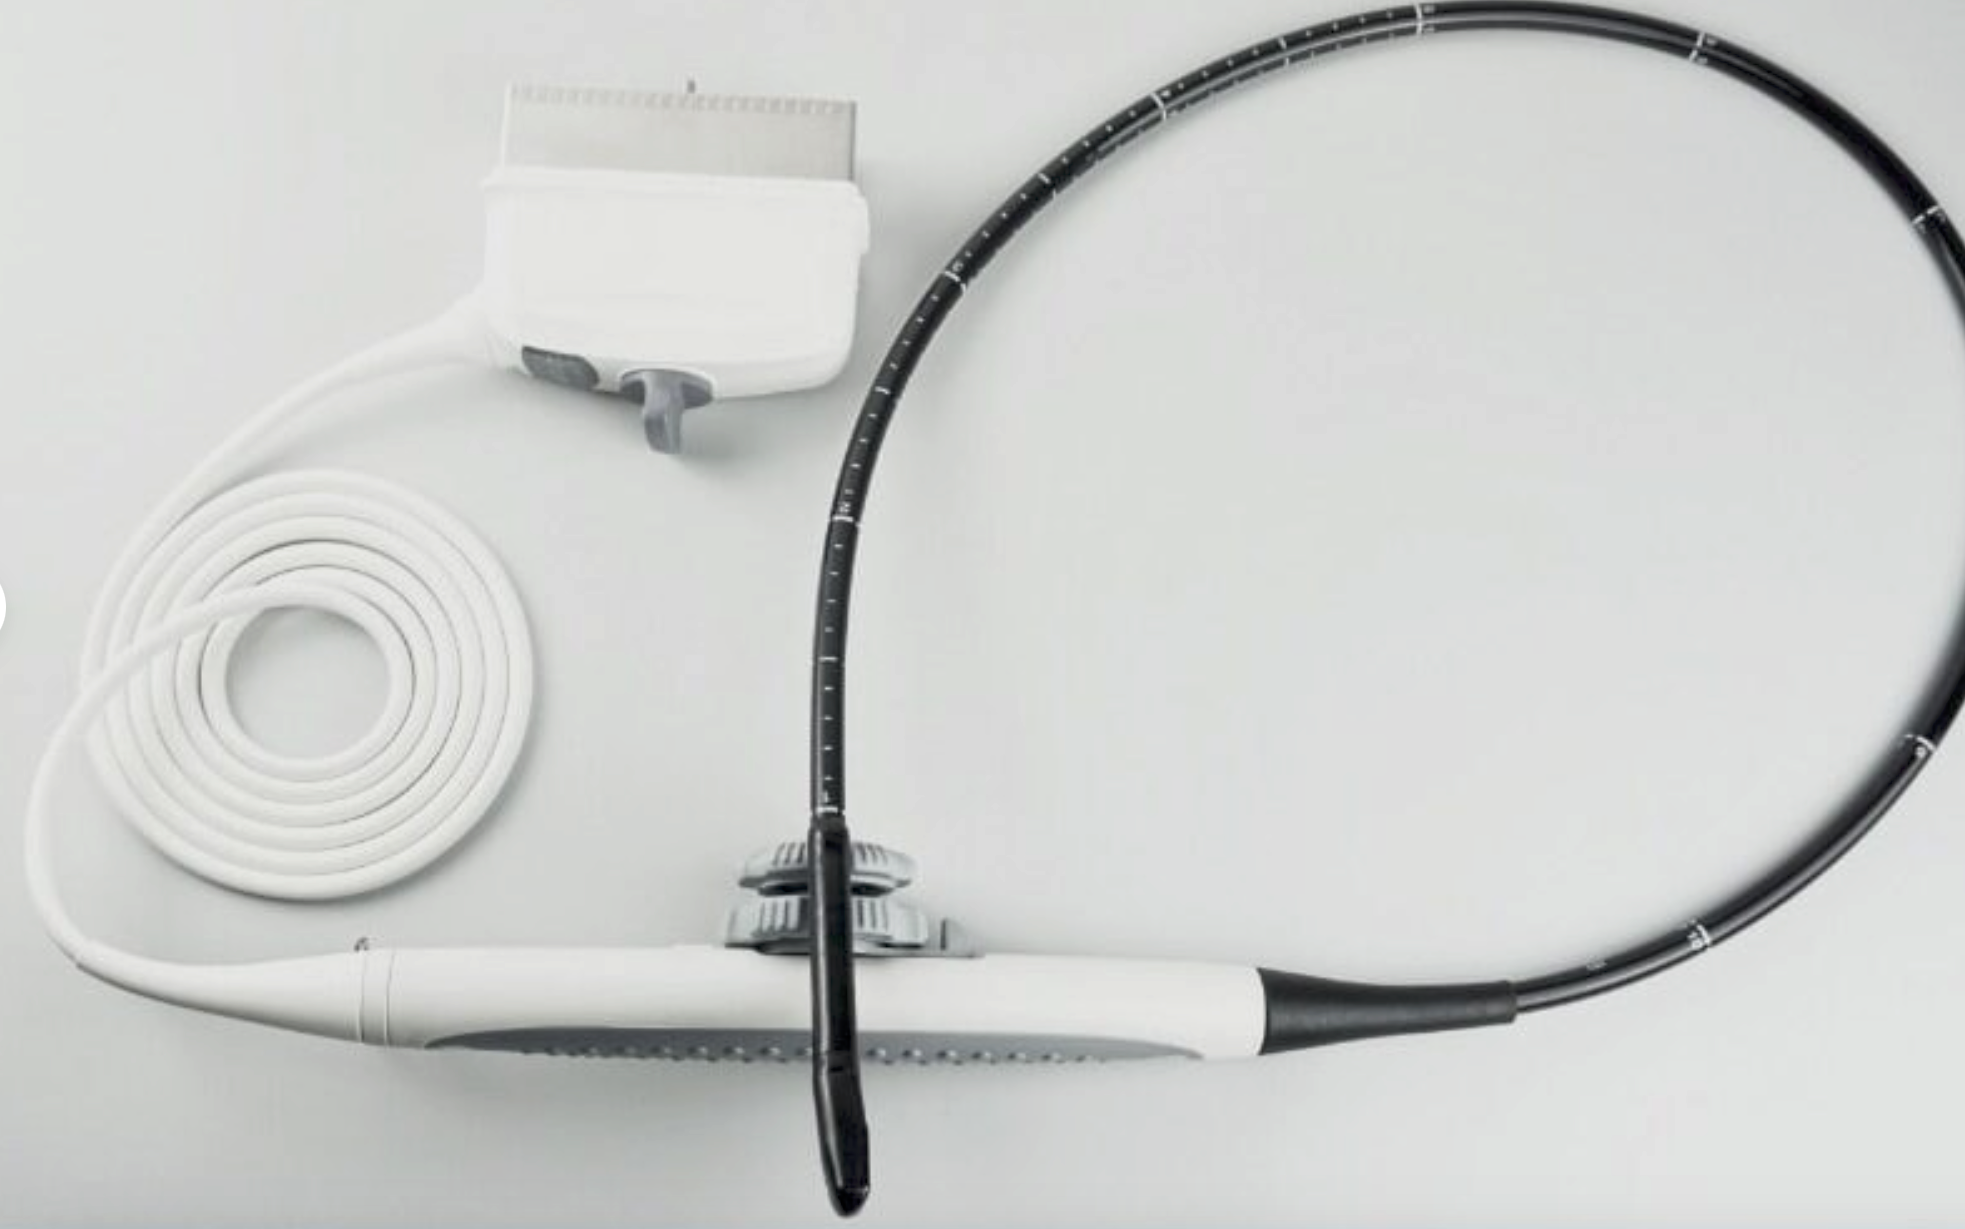

The Laptop Ultrasound Scanner combines cutting-edge technology with portability to enhance your medical practice. This device allows for high-quality ultrasound imaging, ensuring that healthcare professionals can provide accurate diagnoses. Additionally, it features a Transvaginal probe that delivers detailed views of internal structures, making it indispensable for gynecological examinations. Because of its sophisticated design, you can easily operate it in various clinical settings.

With the inclusion of a 3D workstation, the Laptop Ultrasound Scanner offers enhanced imaging capabilities that allow healthcare professionals to view detailed 3D images. This functionality improves diagnostic accuracy and helps in monitoring various conditions over time. Additionally, the software included enables efficient storage and easy retrieval of images, supporting medical professionals in their evaluations. Hence, this scanner not only provides high-quality imaging but also practical functionalities that are essential for modern medical practices.